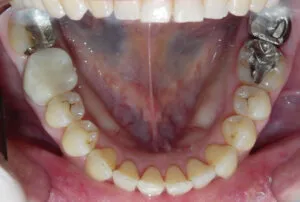

※この写真は、歯牙移植後矯正治療を行い、三年が経過しました。